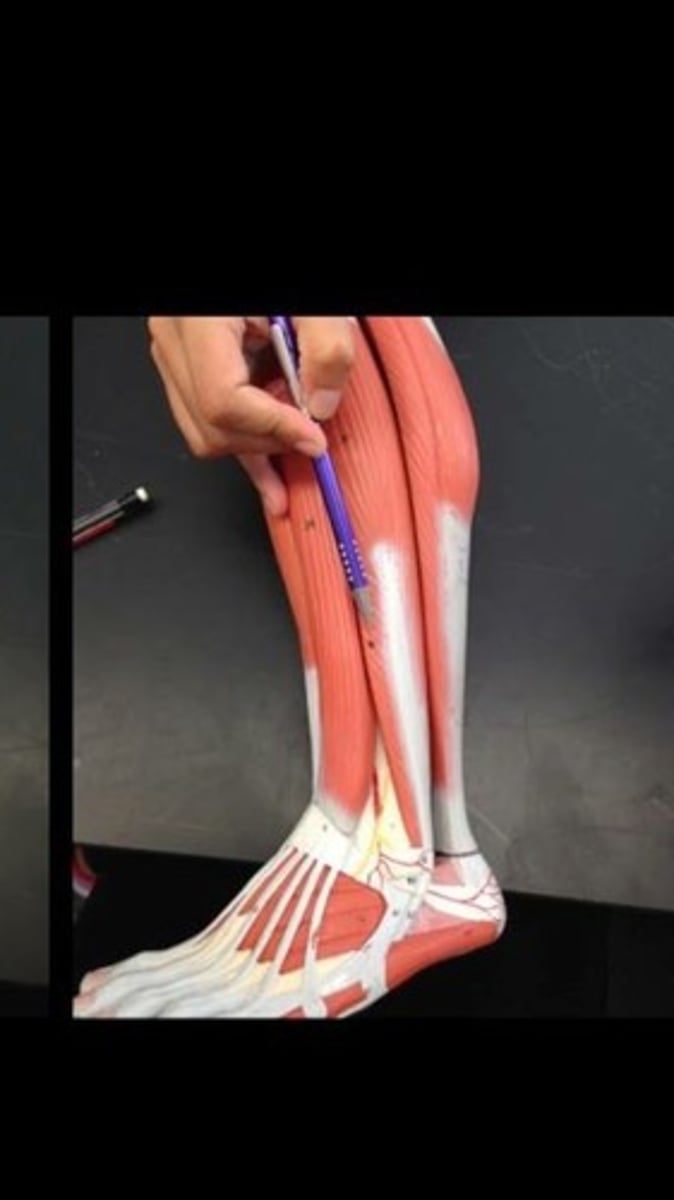

Fibularis brevis

Tibialis anterior

Extensor digitorum longus

Flexor digitorum longus

Fibularis longus

Soleus

Flexor hallucis longus